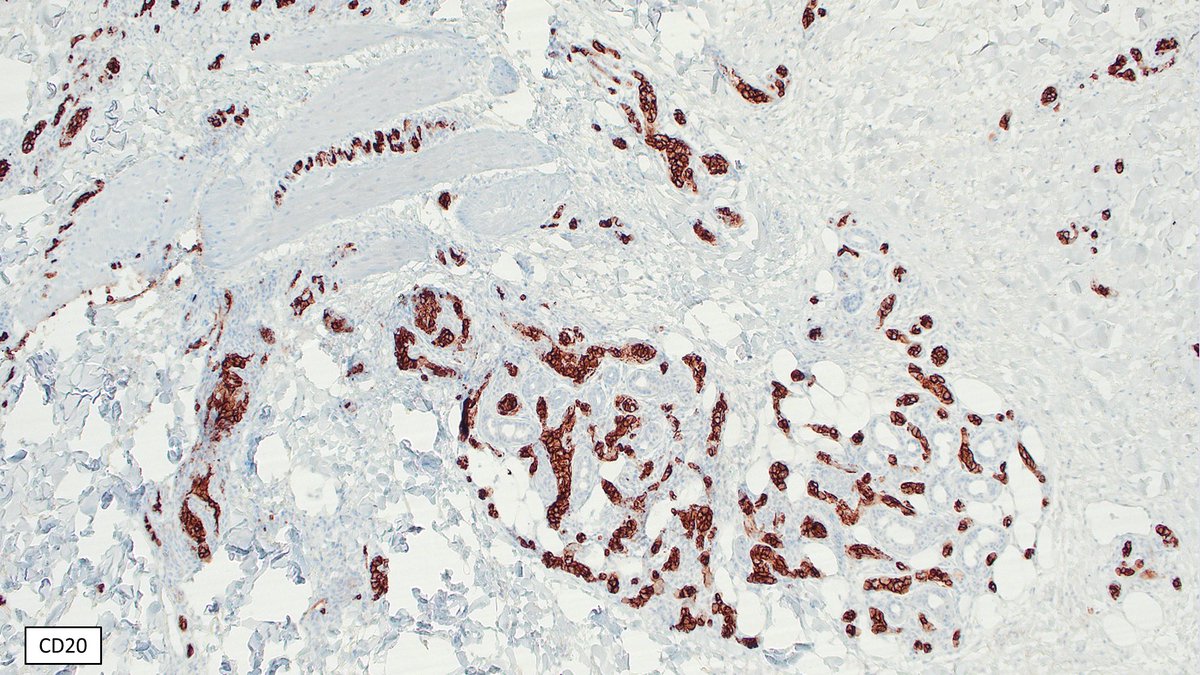

🎉#JI_TopRead ➡️ This study by Pratik Deb, MD, PhD et al. reveals the effects of TLR10 expression in primary #human pDCs. #ReadTheJI #immunology Patricia Fitzgerald-Bocarsly Read here what this means for innate responses: ow.ly/HHVu50TgPNC